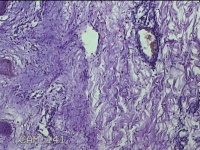

右腋下结节

性别

男

年龄

37岁

临床诊断

腋窝乳糜囊肿

一般病史

发现右腋下结节1年余,近日出现局部红肿及疼痛。

标本名称

大体所见

灰白暗红色组织2.7x1.8x0.8cm一块,表面带梭形皮肤2.8x1.3cm,皮下见结节2.7x1.3cm一个,切开结节呈实性,切面灰白粉红色,质软。

慢性脓肿

皮肤慢性炎症伴局灶性化脓性炎症。

所提供图片不具有诊断价值,炎性病变可能。